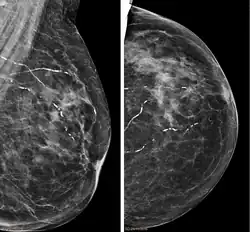

| Right breast mammograms showing several calcified arterioles. Patient 94 years old. | |